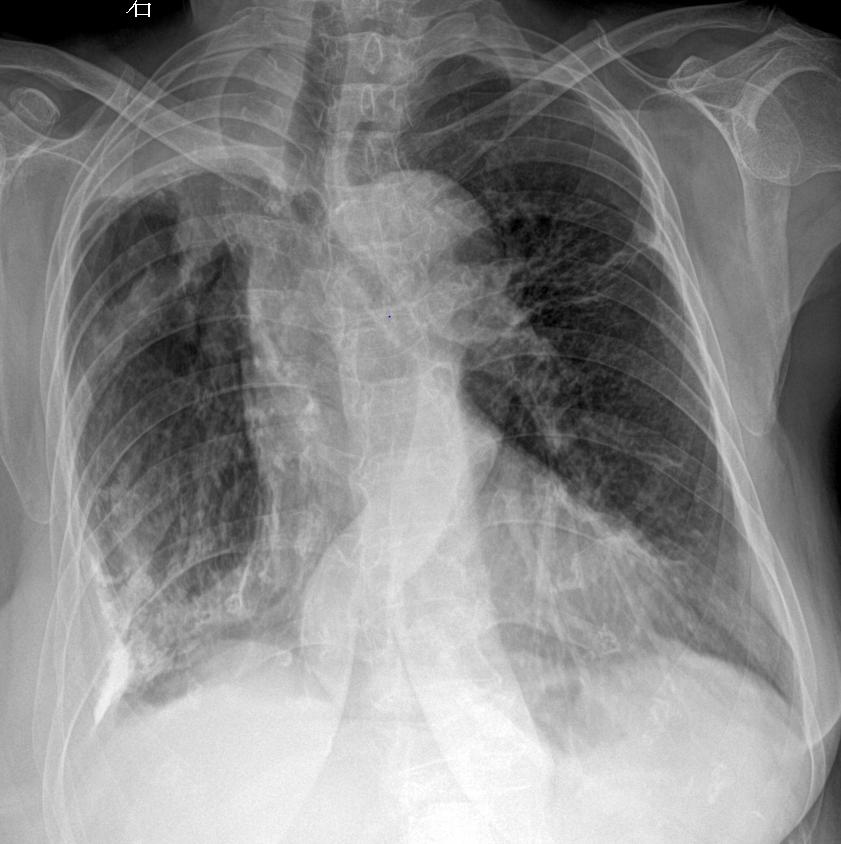

主诉:咳嗽 闷气 男 80y 考虑什么家人们?答案打到评论区

2025-02-25 16:12